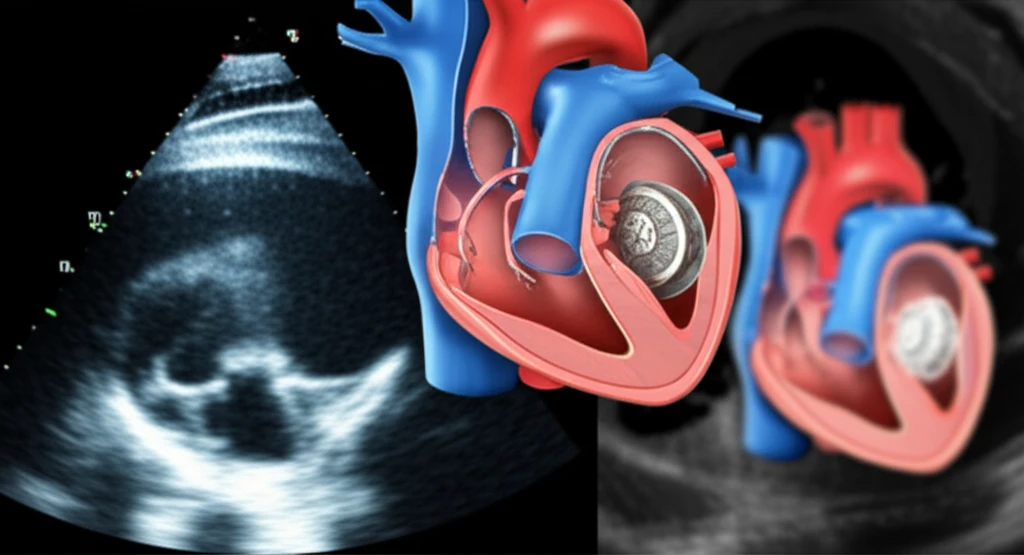

For individuals with non-valvular atrial fibrillation (AFib), the Watchman device offers a life-changing alternative to long-term anticoagulant therapy. This small, implantable device effectively reduces the risk of stroke by sealing off the left atrial appendage (LAA), where blood clots commonly form in AFib patients. However, the success of the Watchman device hinges on one critical factor: accurate sizing.

Implanting a Watchman device that is too small can lead to leaks around the device, leaving patients vulnerable to stroke. Conversely, a device that is too large can increase the risk of complications such as perforation or device migration. Therefore, determining the optimal device size is paramount for ensuring both the safety and efficacy of the procedure.

Traditionally, transesophageal echocardiography (TEE) has been the primary method for measuring the LAA before Watchman implantation. However, recent research suggests that multi-detector computed tomography (MDCT) may offer a more precise and reliable approach to device sizing, potentially leading to improved patient outcomes.